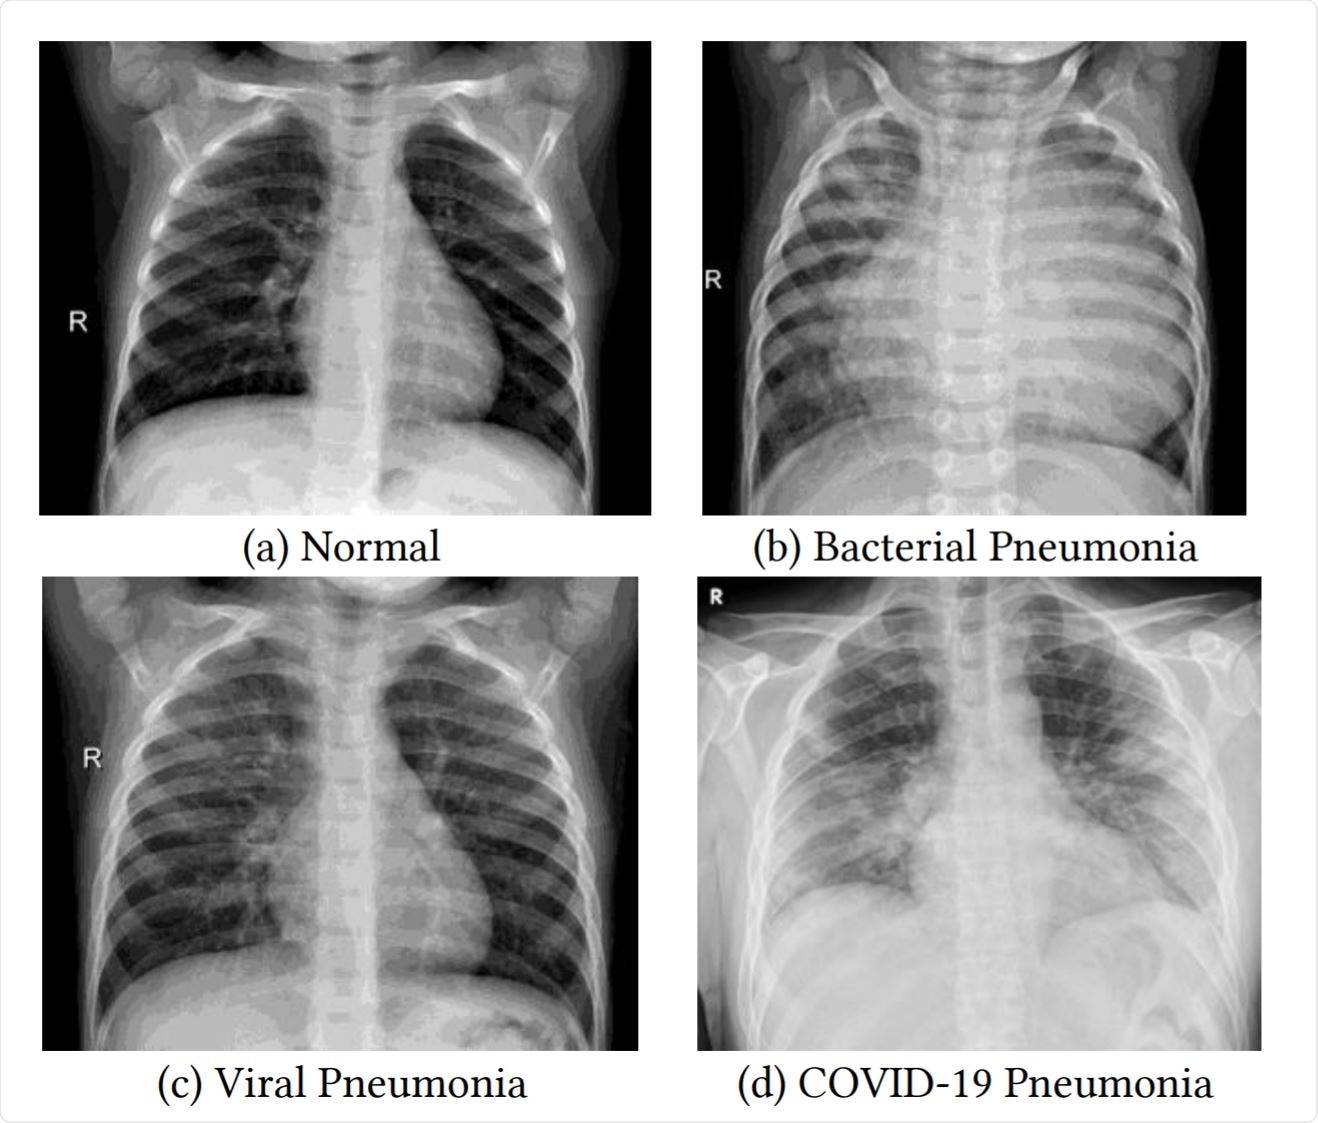

Examples of frontal-view chest X-Ray images from the datasets.

Examples of frontal-view chest X-Ray images from the datasets. Image Credit: https://www.medrxiv.org/content/10.1101/2020.12.14.20248158v1.full.pdf